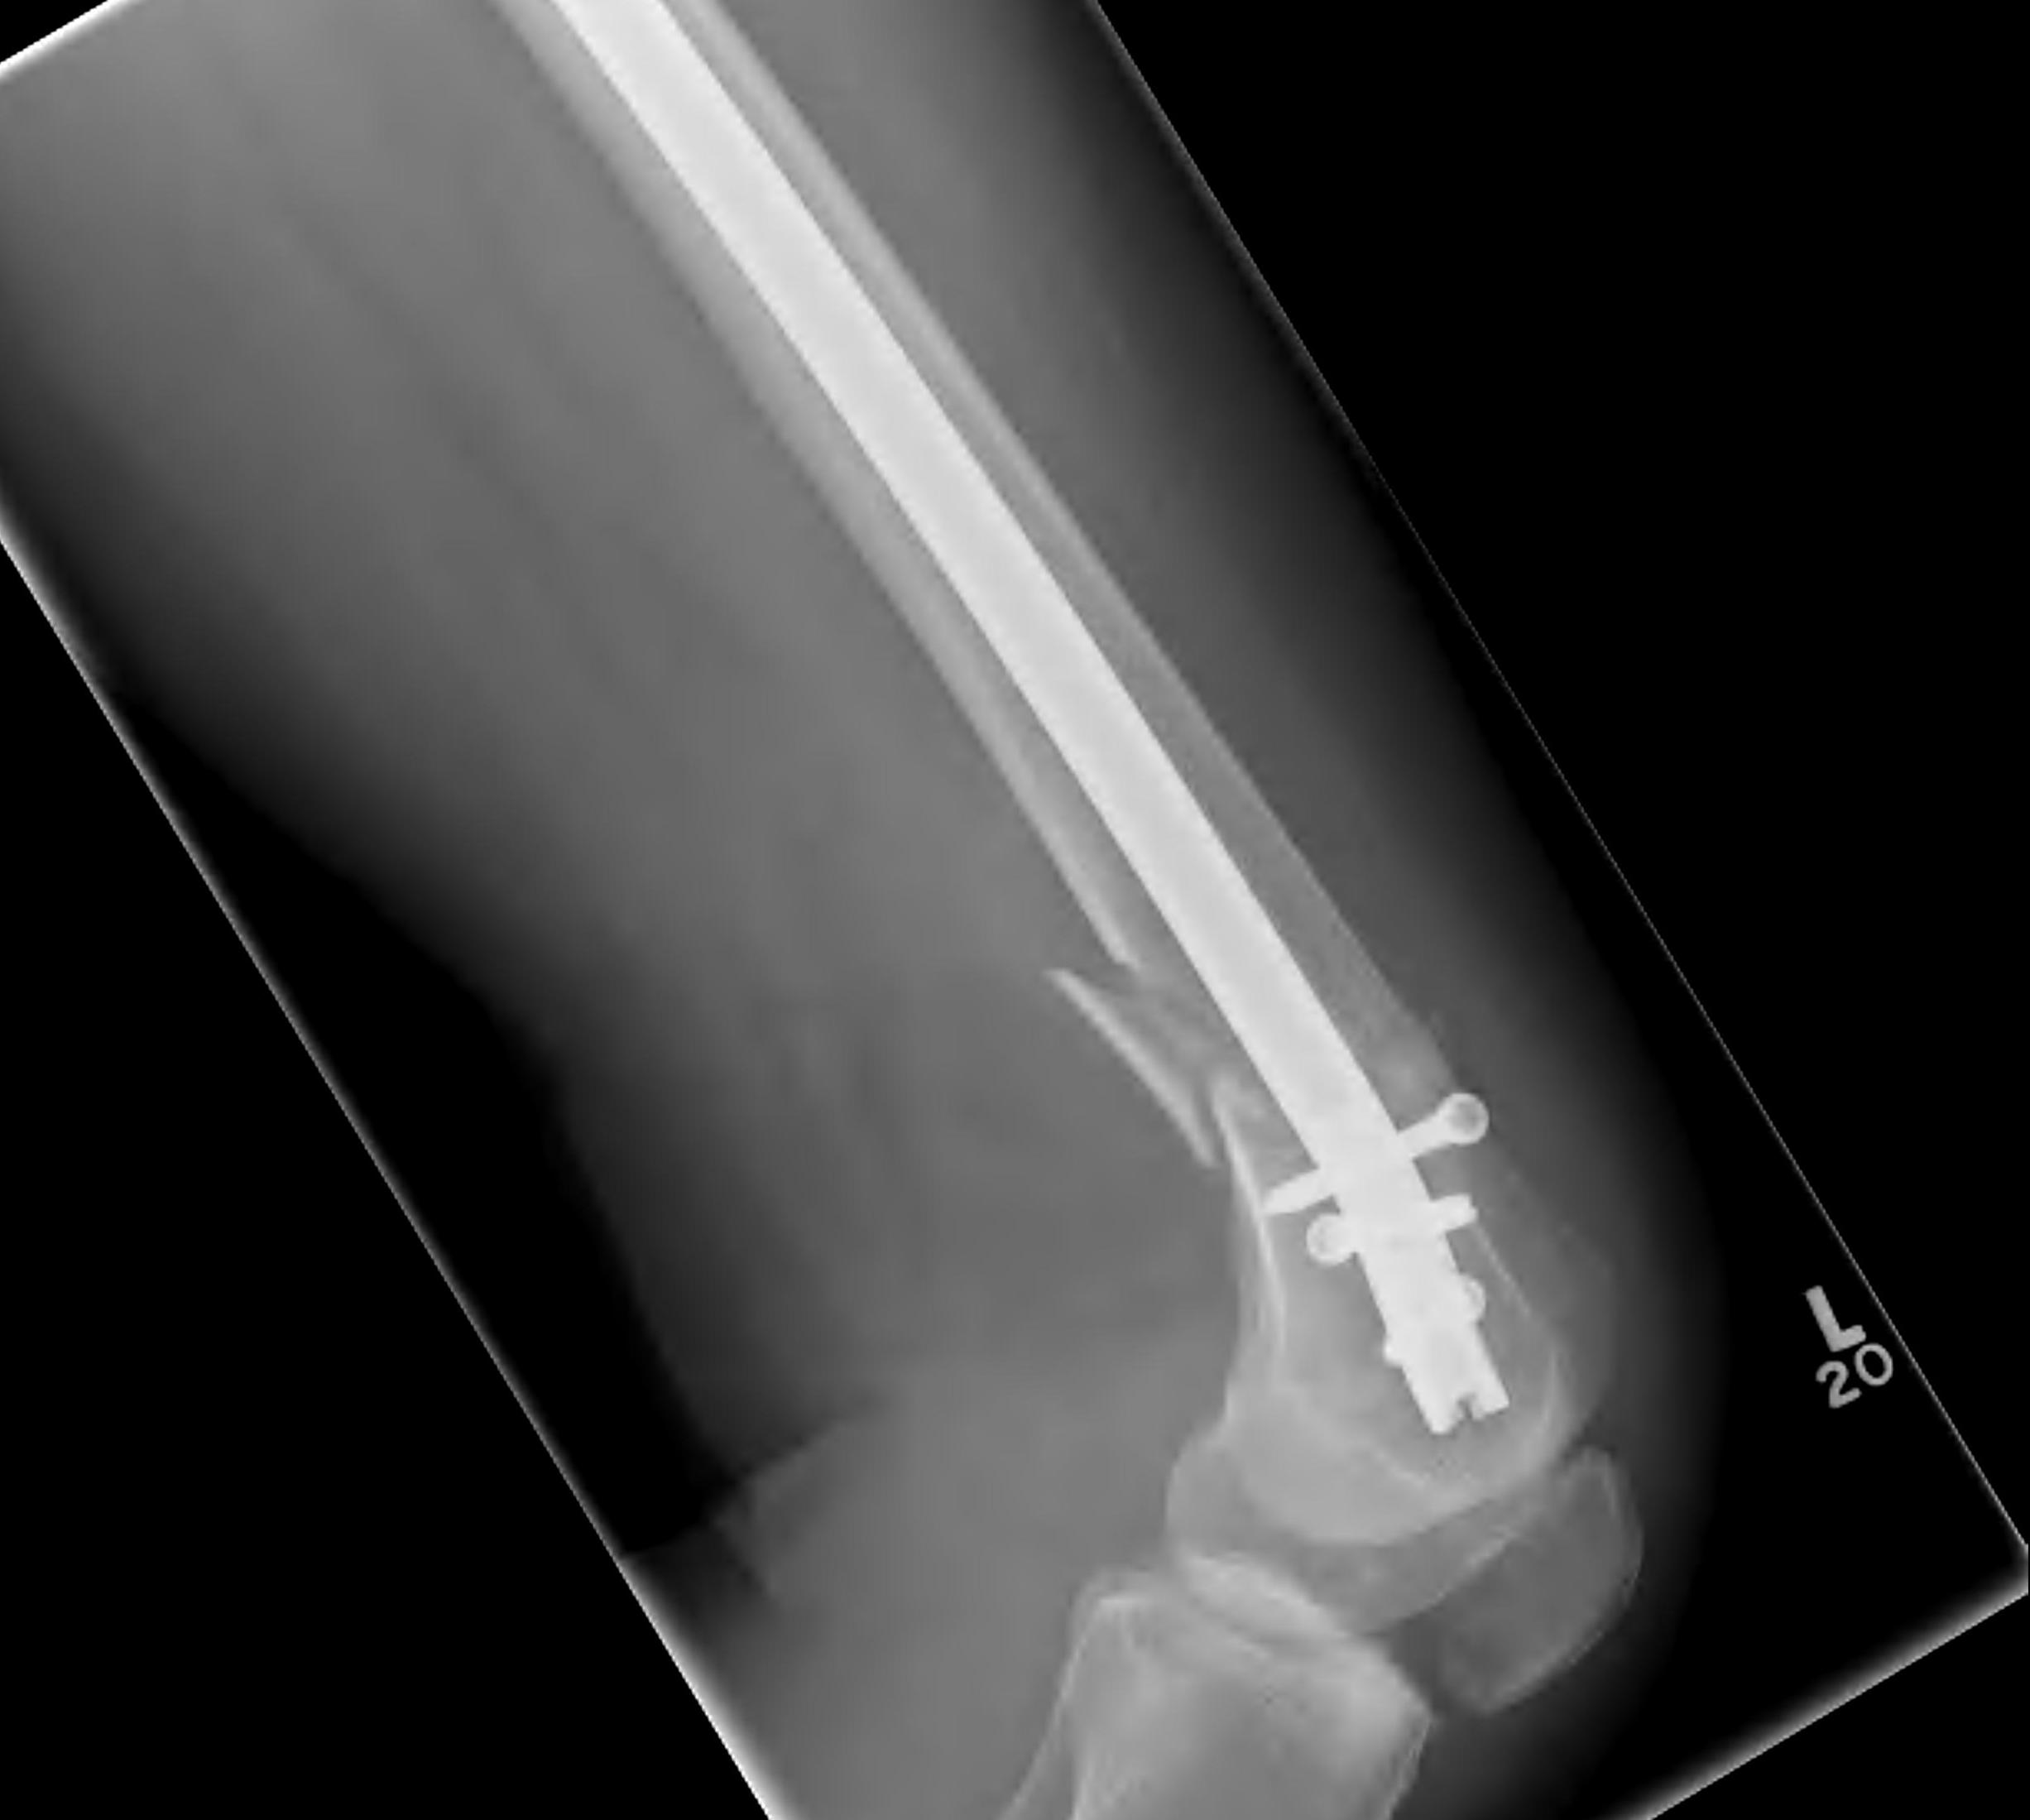

Retrograde Nail

Surgical Technique

Pass guide wire

- consider blocking screws to aid reduction

Blocking screws

Femoral distractor and retrograde nail

Locking screws

- distal locking performed with jig

- proximal AP locking under xray control